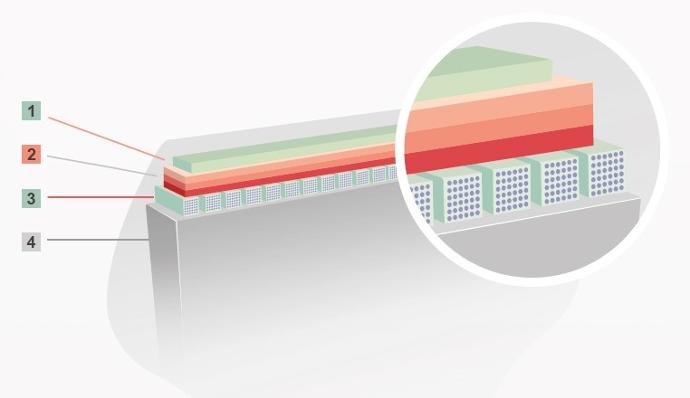

ComboWave трансдюсер с 3T технология

В сравнение с традиционните трансдюсери, ComboWave използват нов тип композитен пиезоелектричен материал за значително оптимизиране на акустичния спектър и намаляване на акустичния импеданс. Интегрирани с уникалната 3T технология на Mindray Animal Care, сензорите ComboWave осигуряват несравнима производителност с изключителна разделителна способност и еднородност на изображението.

Традиционен кристал

Композитен кристал

ComboWave

(композитен кристал с 3T)

1. лещи

2. 3 шумопоглъщащи слоя

3. композитен кристал

4. основен материал

ComboWave Transducer with 3T Technology

Compared to traditional transducers, ComboWave uses a new type of composite piezoelectric material to significantly optimize the acoustic spectrum and reduce acoustic impedance. Further integrated with Mindray Animal Medical's unique 3T technology, the ComboWave transducers allow you to experience outstanding performance with extreme image resolution and uniformity.

Traditional crystal

Composite crystal

ComboWave

(Composite crytal with 3T technology)

1. Lens

2. 3 Matching layers

3. Composite crytal

4. Backing material